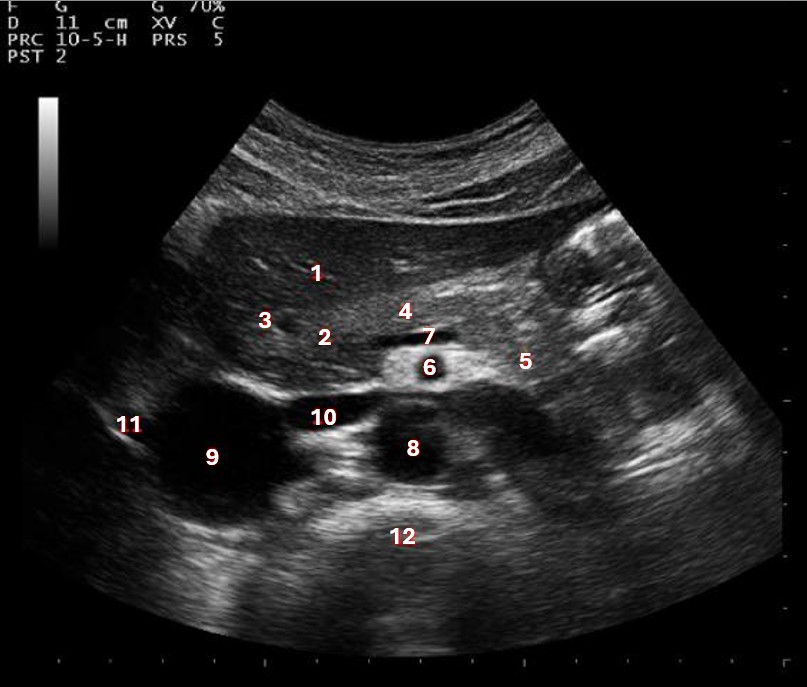

Which of the following structures is labeled #5?

lateral left lobe |

What lobe of the liver is indicated by #1?

posterior right lobe

What structure/vessel is indicated by #8?

medial left lobe |

What lobe of the liver is indicated by #2?

anterior right lobe |

Which of the following structures is labeled #7?

anterior right lobe |

What structure/vessel is indicated by #12?

spine

Which of the following structures is labeled #6?

medial left lobe |

Which of the following structures is labeled #3?

IVC

Which of the following structures is labeled #8?

posterior right lobe |